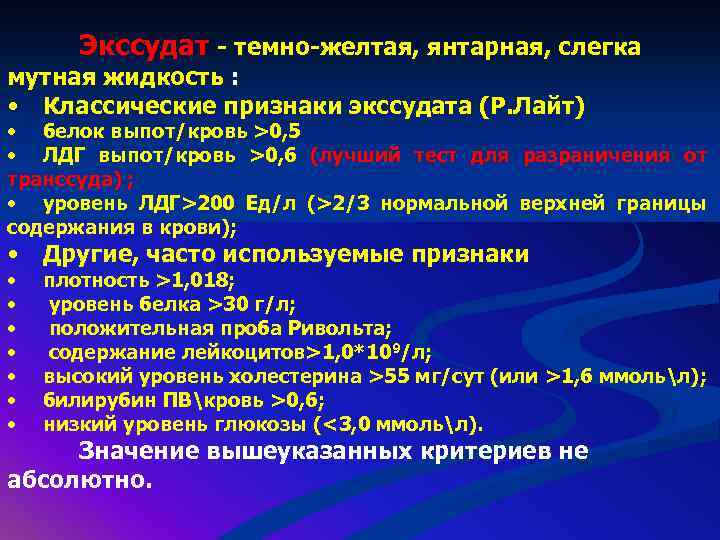

Диагностика плеврального выпота: что нужно знать